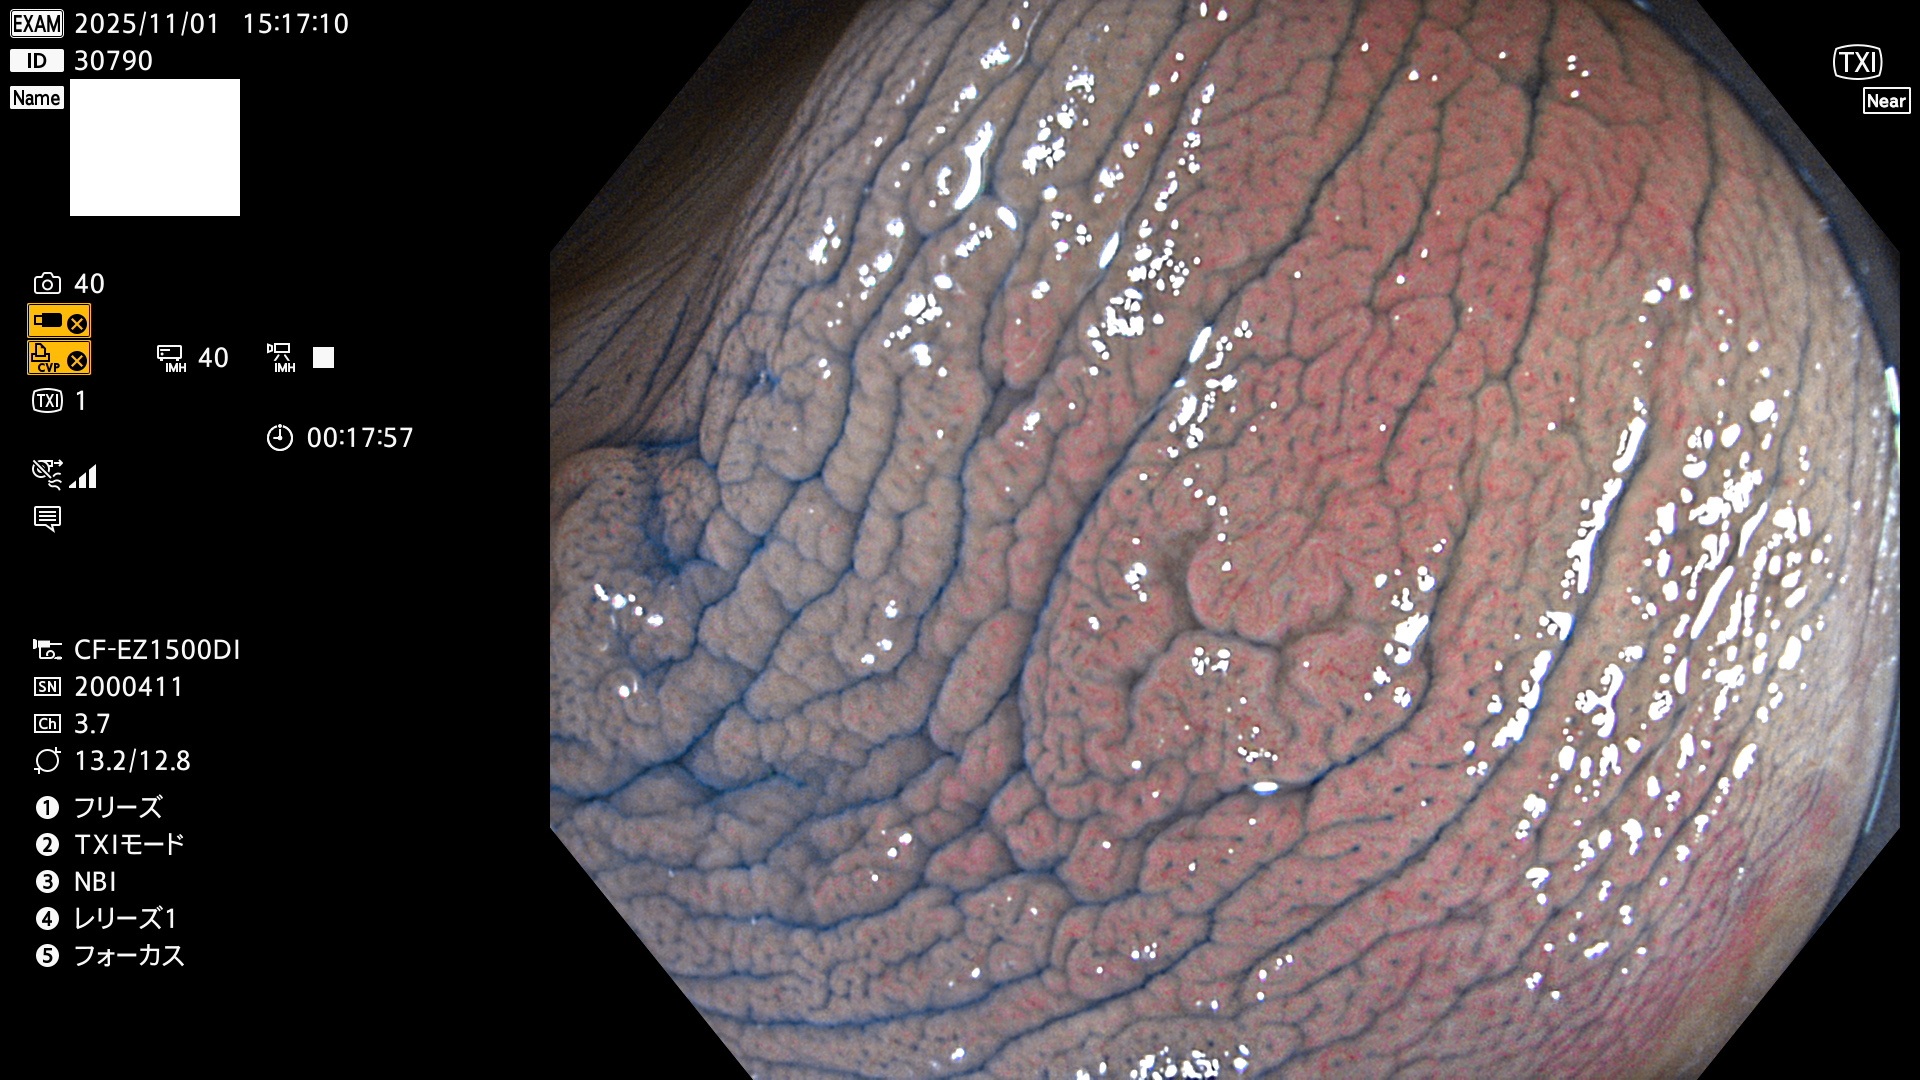

完全に平坦な物をUb、陥凹している物をUcと呼びます。Ubは認識が困難で、Ucはびらん(炎症)と紛らわしいために見落とされやすく、「内視鏡後・大腸癌」の原因になります。

専門的)Uc=De Novo癌? 内視鏡の解像度が低かった時代、このような説もありました。しかし今日の高精度内視鏡では良性の微小なUc型腺腫(APC遺伝子異常の腺腫)が日常的に見つかります。Ucこそが多段階発癌(Adenoma-Carcinoma Sequence)のMain Routeです。

毎週の検査(木・金・土・日)に発見されたUbとUc型・腺腫を、その週の日曜の夜にUPし1週間、提示します。

2025年10月30日〜11月2日の4日間(40件)9個 (Uc_ADR=9個/40人=23%)